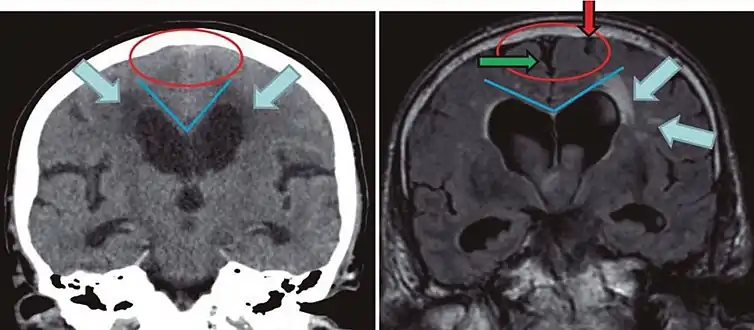

CT and MRI are most commonly used to observe the brain for cerebral atrophy. A CT scan takes cross sectional images of the brain using X-rays, while an MRI uses a magnetic field. With both measures, multiple images can be compared to see if there is a loss in brain volume over time.[20]

Cerebral atrophy can be hard to distinguish from hydrocephalus because both cerebral atrophy and hydrocephalus involve an increase in cerebrospinal fluid (CSF) volume. In cerebral atrophy, this increase in CSF volume comes as a result of the decrease in cortical volume. In hydrocephalus, the increase in volume happens due to the CSF itself.[20]

| Normal pressure hydrocephalus | Brain atrophy | |

|---|---|---|

| Preferable projection | Coronal plane at the level of the posterior commissure of the brain. | |

| Modality in this example | CT | MRI |

| CSF spaces over the convexity near the vertex (red ellipse | Narrowed convexity ("tight convexity") as well as medial cisterns | Widened vertex (red arrow) and medial cisterns (green arrow) |

| Callosal angle (blue V) | Acute angle | Obtuse angle |

| Most likely cause of leucoaraiosis (periventricular signal alterations, blue arrows |

Transependymal cerebrospinal fluid diapedesis | Vascular encephalopathy, in this case suggested by unilateral occurrence |